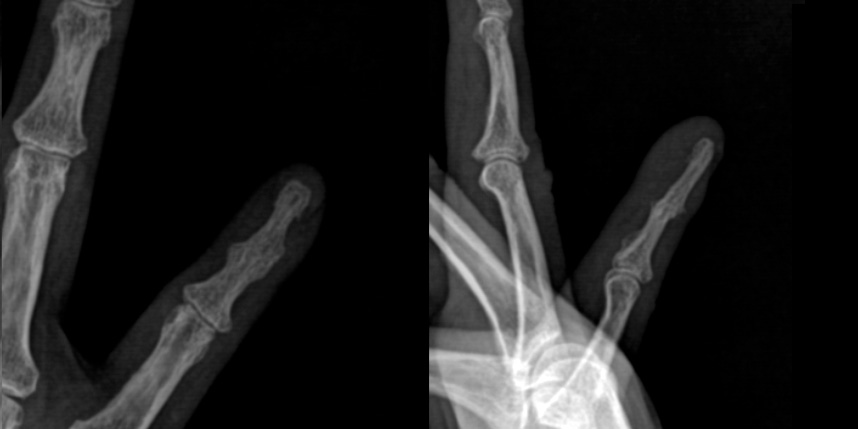

단순히 끝마디 관절염만 있을 때 골극 절제술을 잘 시행하지는 않지만 점액낭종이 생겨 손톱 변형이 있고 통증이 있을 때 점액낭종 절제술과 함께 골극 절제술을 같이 시행해볼 수 있습니다.

점액 낭종은 손가락에서 생기는 결절종이기 때문에 결절종과 마찬가지로 다음 사진처럼

관절과 연결된 뿌리를 잘 찾아가서 제거해주는 것이 재발을 줄이는 방법입니다.

피부가 얇아져 있어서 피부를 일부 같이 포함하여 절제하는데, 피부 결손이 큰 경우 피부 이식이 필요한 경우도 있습니다.